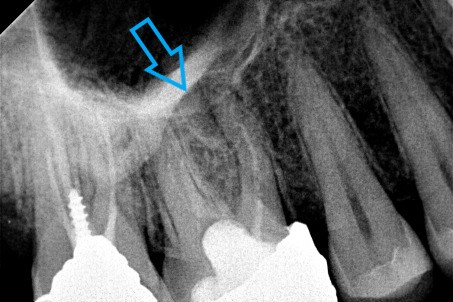

Ο ασθενής επιθυμούσε την προσθετική αποκατάσταση (με θήκη / στεφάνη δοντιού) του πρώτου γομφίου στην αριστερή πλευρά της κάτω γνάθου, καθώς το δόντι αυτό είχε ένα παλιό σφράγισμα το οποίο συνεχώς έσπαζε. Απαραίτητη προϋπόθεση για την έναρξη της διαδικασίας για τη στεφάνη δοντιού ήταν η κλινική και ακτινογραφική εξέταση του γομφίου. Μετά τη λήψη ακτινογραφίας αποκαλύφθηκε οτι το δόντι είχε μία παλιά απονεύρωση, η οποία ήταν ατελής εφόσον δεν εκτεινόταν σε όλο το μήκος των ριζικών σωλήνων του δοντιού ενώ φαινόταν ο τρίτος ριζικός σωλήνας στο δόντι να μην έχει εντοπιστεί. Μετά από συνεννόηση με τον ασθενή αποφασίστηκε η επανάληψη της απονεύρωσης του δοντιού, ώστε να εξασφαλιστεί ένα εγγυημένο προσθετικό αποτέλεσμα. Γενικότερα είναι επιθυμητό οι προσθετικές εργασίες να τοποθετούνται στα δόντια εφόσον έχουν γίνει όλες οι απαραίτητες εργασίες όπως απονεύρωση δοντιού, καθαρισμός των ούλων κ.α.

Μετά λοιπόν την αφαίρεση του παλιού σφραγίσματος εντοπίστηκε ο τρίτος ριζικός σωλήνας που δεν είχε βρεθεί στην παλιά πρώτη απονεύρωση, όπως δείχνει και η φωτογραφία της αρχικής κλινικής εικόνας. Στη συνέχεια καθαρίστηκαν και επεξεργάστηκαν όλοι οι ριζικοί σωλήνες (Για περισσότερες πληροφορίες Βλέπε Επανάληψη απονεύρωσης). Η διαδικασία ολοκληρώθηκε με την έμφραξη των ριζικών σωλήνων του δοντιού και την ανασύσταση της εκτεταμένης κοιλότητας με ειδικό άξονα υαλονημάτων και ρητίνη. Ακολούθως το δόντι τροχίστηκε, λήφθηκαν αποτυπώματα και όταν ο οδοντοτεχνίτης είχε έτοιμη τη θήκη του δοντιού αυτή κολλήθηκε στο δόντι.

ΠΡΙΝ